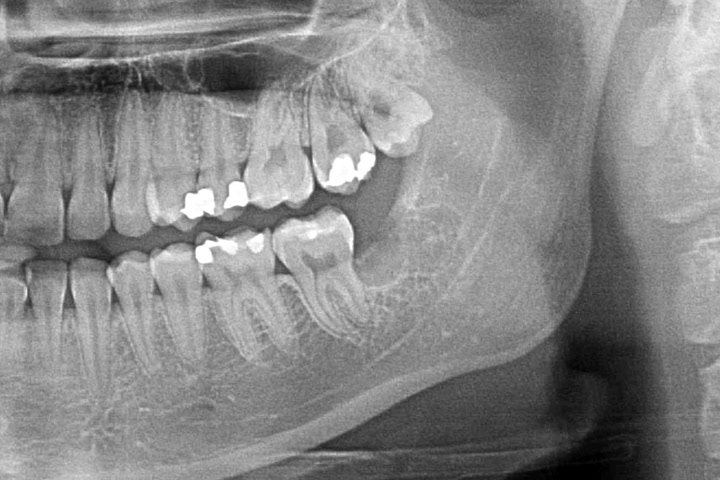

"Czy należy usuwać zęby mądrości?"- to często pojawiające się w gabinecie stomatologicznym pytanie. Każdy przypadek warto rozważyć indywidualnie, ale w większości odpowiedź brzmi: "tak". Wynika to z faktu, że ósemki często generują problemy samą swoją obecnością w jamie ustnej- niekoniecznie dlatego, że są popsute. U wielu osób zdarza się, że po prostu brakuje przestrzeni w szczęce lub żuchwie, dla prawidłowego wyżynania się i pozycjonowania tych zębów. W tym wypadku ósemki górne wrastają w policzki, a dolne blokują się pomiędzy kątem żuchwy a siódemkami dolnymi. Powoduje to po pierwsze, że zęby te generują znaczne siły działające na zęby sąsiednie często prowadząc do zniszczenia ich korzeni. Ponieważ dzieje się to w kości czasem trudno pacjentowi w porę wyczuć ten problem i dochodzi do utraty bardzo istotnych zębów nr 7. Po drugie może utrudniać higienizację ósemek, ale i siódemek co prowadzi do szybko rozwijającej się próchnicy. Po trzecie może prowadzić do stłoczenia zębów lub wykrzywiania ich w całym łuku zębowym. Kolejnym problemem może być często pojawiający się bolesny stan zapalny dziąsła- ponad rosnącą ósemką tworzy się kaptur z błony śluzowej, który zostaje zainfekowany przez zalegające bakterie z resztek pokarmowych. Nieprawidłowa pozycja ósemek sprzyja także przygryzaniu policzków co może prowadzić do powstawania w miejscach urażanych tzw. leukoplakii. Jest to schorzenie objawiające się białym rogowaceniem nabłonka jamy ustnej, a znaczny odsetek tych zmian przekształca się w nowotwór. Kolejnym przykładem na problem generowany pozostawionymi zębami mądrości są tzw. torbiele zawiązkowe powstające na bazie zawiązków tych zębów. Torbiele te nie wykryte w porę, poprzez rozrost, prowadzą do znacznych ubytków kości co grozi złamaniami np żuchwy.

PRZYKŁAD 3